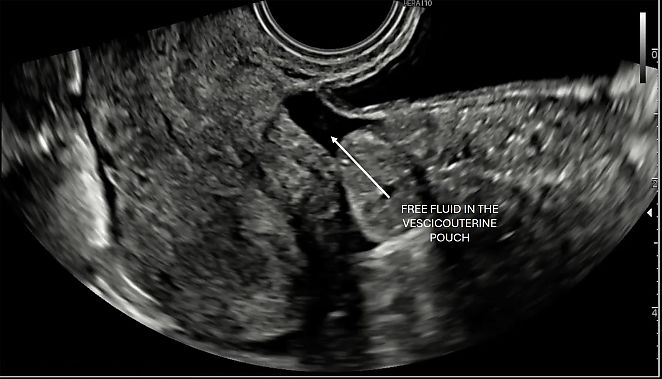

Vesicouterine pouch and pouch of Douglas

The vesicouterine pouch is an extension of the peritoneal cavity located between the bladder and the anterior wall of the uterus. It can be easily identified, particularly when a small amount of fluid collects within it (Figure 7).

7

Vesicouterine pouch.